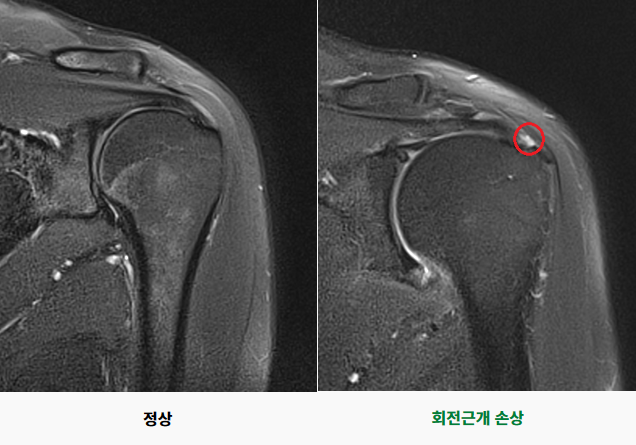

회전근개 손상

회전근개는 어깨와 팔을 연결하는 4개의 힘줄(견갑하근, 극상근, 극하근, 소원근)로, 팔의 회전 운동에 관여하고, 상완골두를 관절와로 압박하여 견관절 안정성에 중요한 역할을 합니다. 회전근개 손상은 이 힘줄의 손상을 의미합니다. 어깨 관절에 발생하는 만성 통증의 가장 흔한 원인 중 하나로 주로 퇴행성 변화, 외상, 어깨의 과사용 등으로 인하여 발생합니다.